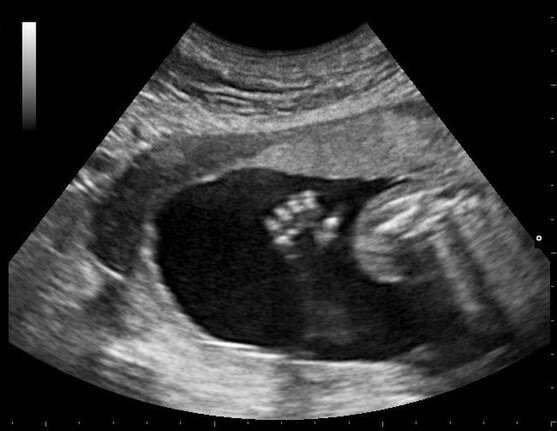

拍摄于SCP-3145-JP发生前的B超影片

描述:SCP-3145-JP指代2024年10月22日美国居民Susan Buer(26岁)因前置胎盘1接受剖腹产手术时发生的异常现象。异常发生前对Susan的体检并未发现异常,且Susan、其夫Tyler及双方亲属均不具异常性质。